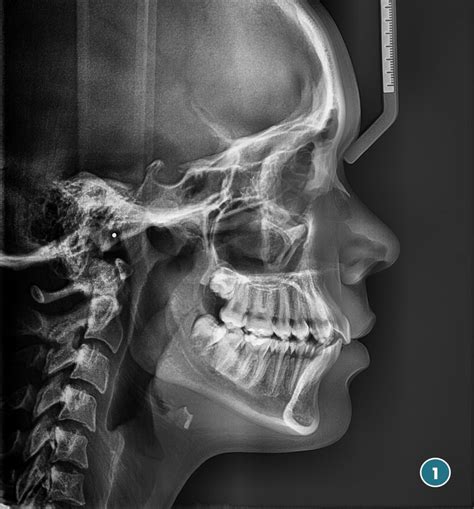

3. Telerradiografía o RX Lateral de Cráneo

A través de la telerradiografía se podrá obtener información de la relación anteroposterior entre maxilares, así como información acerca de la inclinación de los dientes.